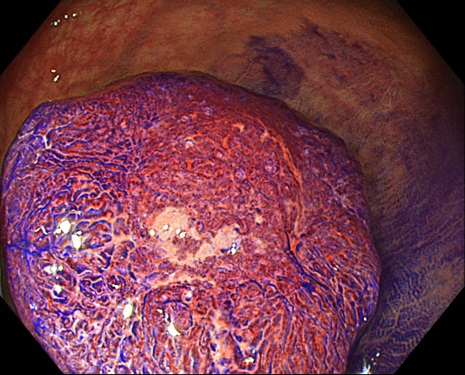

In practice, in pit pattern observation, lesions with highly irregular VI pit pattern are often difficult to evaluate with Near mode in previous Dual Focus function models. However, we have an impression that the Near mode of CF-EZ1500D can exhibit as good image quality as magnifying observations with manual zoom scopes, which helps us evaluate lesion in these difficult cases. Similarly, in magnifying observations under NBI, surface and vessel patterns can be observed very clearly in the Near mode with the CF-EZ1500D (Fig. 3a). These impressions suggest that the magnifying observation with CF-EZ1500D exhibits diagnostic accuracy equivalent to that of the manual zoom scopes in diagnoses based on the JNET classification5-7)

NBI

Fig. 3(a)

<Fig. 3> Endoscopic images of a node in Near mode using CF-EZ1500D The vessel and surface patterns at the top of the node have been disturbed and are considered to correspond with Type 3 in the JNET classification (a). Magnifying chromoendoscopy with crystal violet staining under TXI mode 2 visualized highly irregular VI pit pattern (invasive pattern) and a partial type VN pit pattern (b).